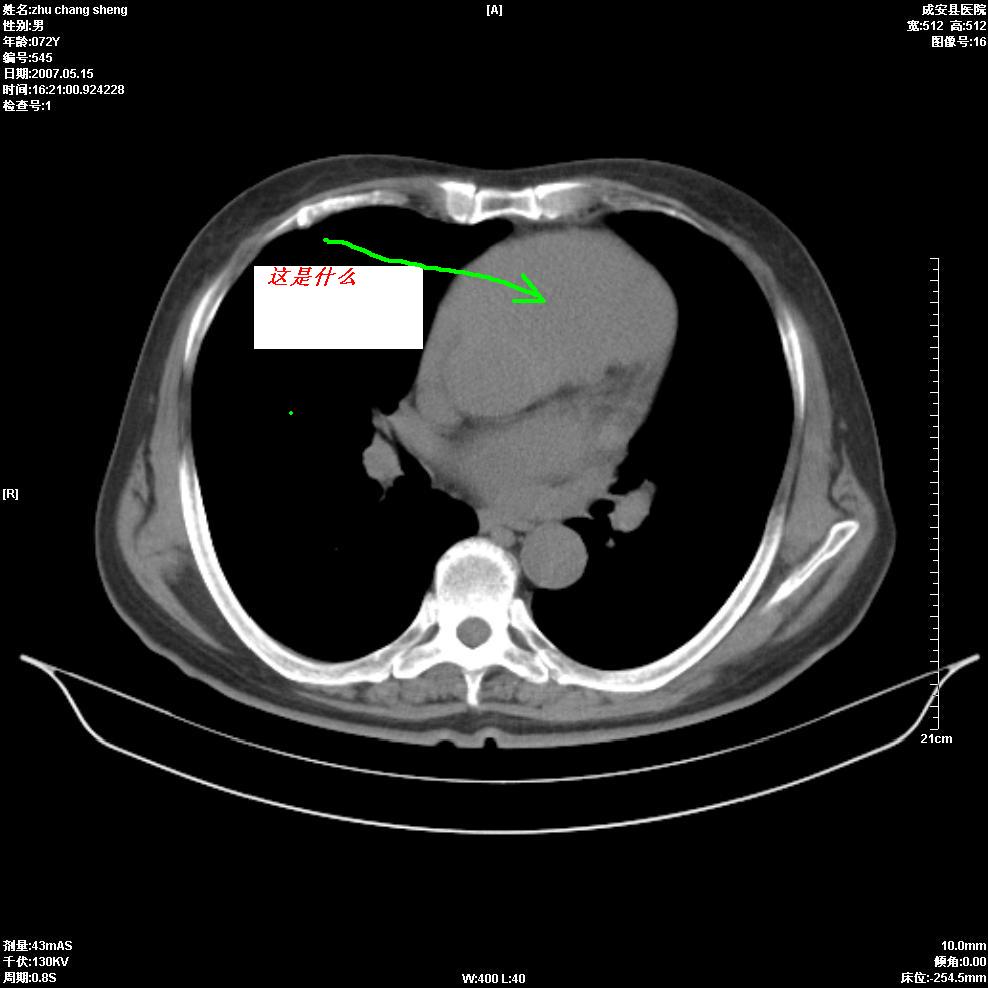

以下是引用医博云天在2007-5-15 19:10:00的发言:[br]心包积液,胸腔积液,心影增大,左心为主。

以下是引用zhangzhongshou在2007-5-15 20:21:00的发言:[br]心包积液可以肯定有,肿块显示不清,建议增强或mri检查。

以下是引用jinning在2007-5-15 21:06:00的发言:[br]心包积液可以肯定,建议增强或mri检查吧!

以下是引用拾荒者在2007-5-15 22:28:00的发言:[br]心包膜增厚,有少量积液,右室前壁示均匀软组织密度影,边界欠清,建议增强扫描或mri检查与室壁瘤鉴别。

以下是引用还珠格格在2007-5-19 9:50:00的发言:[br]病人与5月18日 做了核磁增强扫描 确诊为前上纵隔侵袭性胸腺瘤。